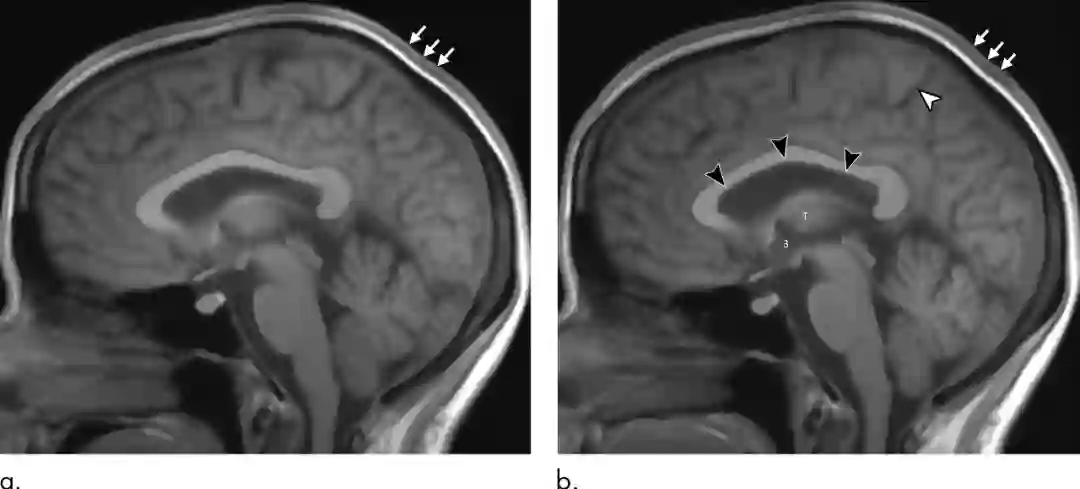

(a)同一宇航员飞行前基线图像和(b)飞行后匹配图像(飞行后第1天)。黑色箭头显示侧脑室前、中、后上缘向上扩展,并伴有扣带沟边缘沟的缩小(白色箭头)

事实上,改变的不仅仅是脑垂体的形状。克雷默博士还表示说:“我们发现,宇航员在飞行后脑垂体位置的高度下降,并且比飞行前更小。此外,没有经历过微重力的宇航员中的脑下垂体的穹丘主要是凸出的,但是,飞行后的宇航员的脑垂体会出现平坦或凹陷的迹象。当然,这种变形也是由颅内压升高而导致的。”